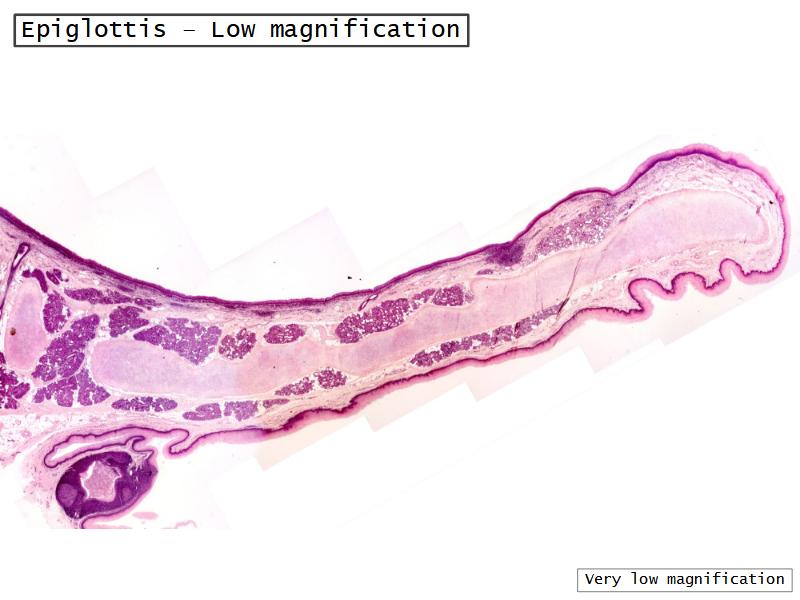

- Slide 111: Epiglottis

Epiglottis